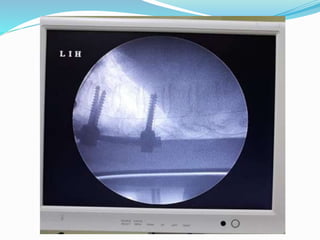

The document discusses spasticity and its treatments. It defines spasticity as increased resistance to passive movement caused by hyperactive stretch reflexes. Treatments mentioned include oral medications, intrathecal baclofen therapy using an implanted pump, selective dorsal rhizotomy neurosurgery, and orthopedic procedures. Intrathecal baclofen therapy involves testing patients by injecting baclofen and monitoring response, then implanting a pump if symptoms improve. Programming the pump involves setting dosage and mode of delivery. Complications are also summarized.